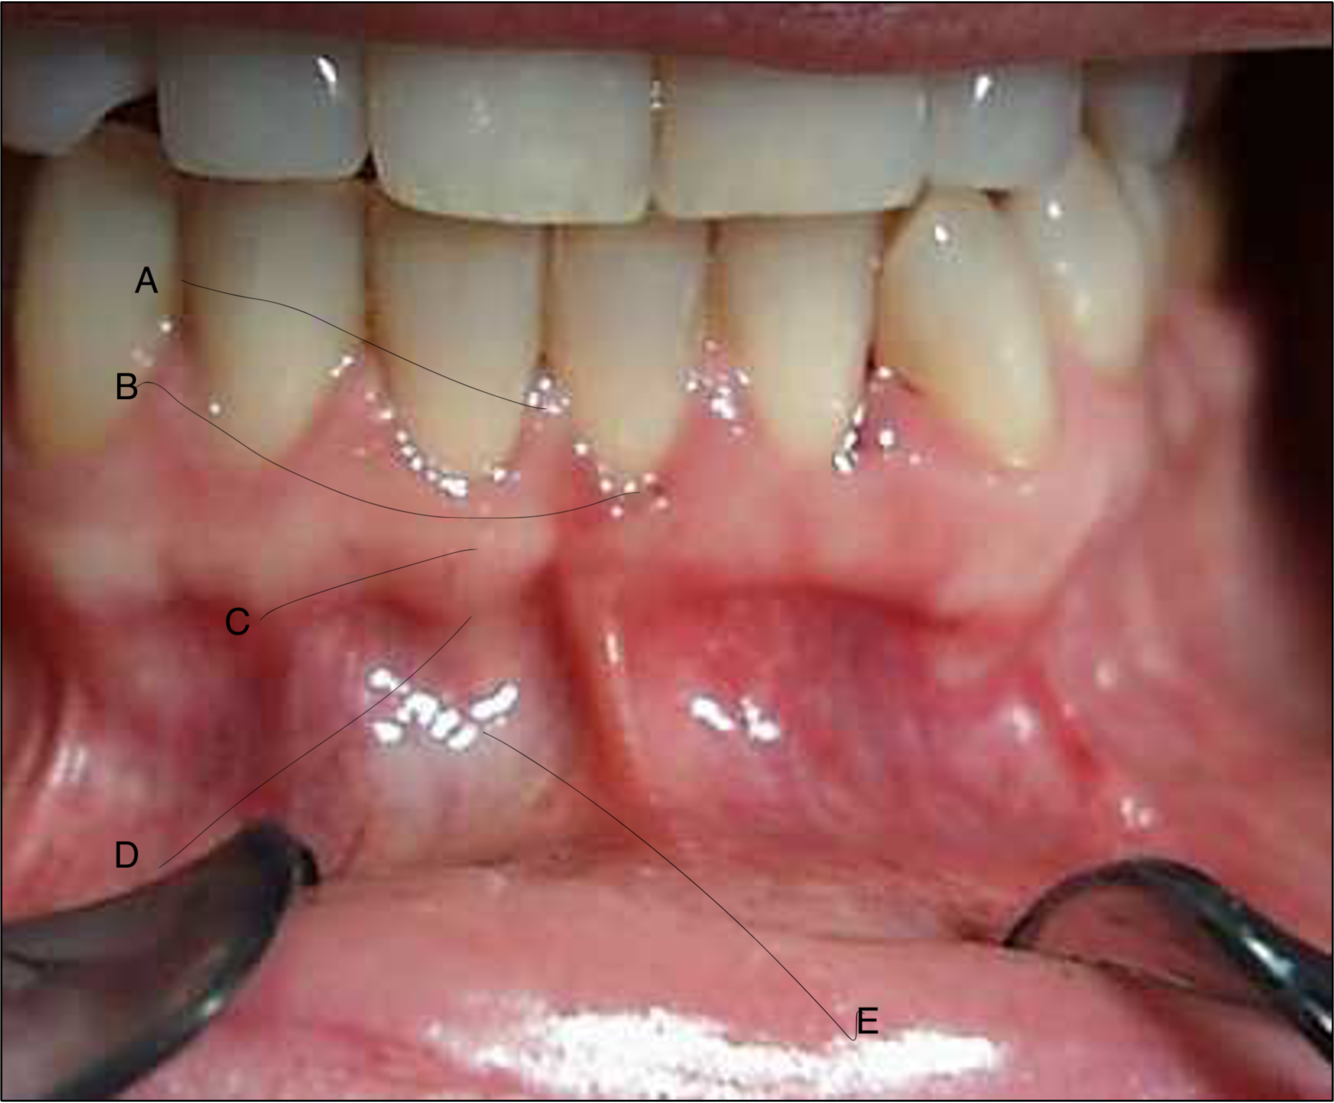

What are the following structures commonly known as?

What structure is labelled A on the photo?

interdental papilla

What structure is labelled B on the photo?

marginal gingivae

What structure is labelled C on the photo?

attached gingivae

What structure is labelled D on the photo?

muco-gingival junction

What structure is labelled E on the photo?

oral/alveolar mucosa